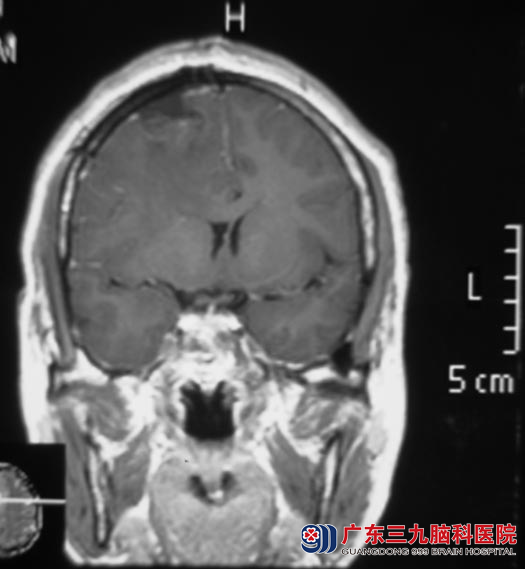

12月4日,鲁明主任主刀,在全麻下行右侧额部凸面脑膜瘤切除术,术中见硬膜下与硬膜粘连紧密的肿瘤组织,灰红色、质韧、血供丰富、与周围边界清楚,显微镜下达辛普森I级切除。现已康复出院。病理结果为:过渡型脑膜瘤(WHO I 级)。

▲手术后